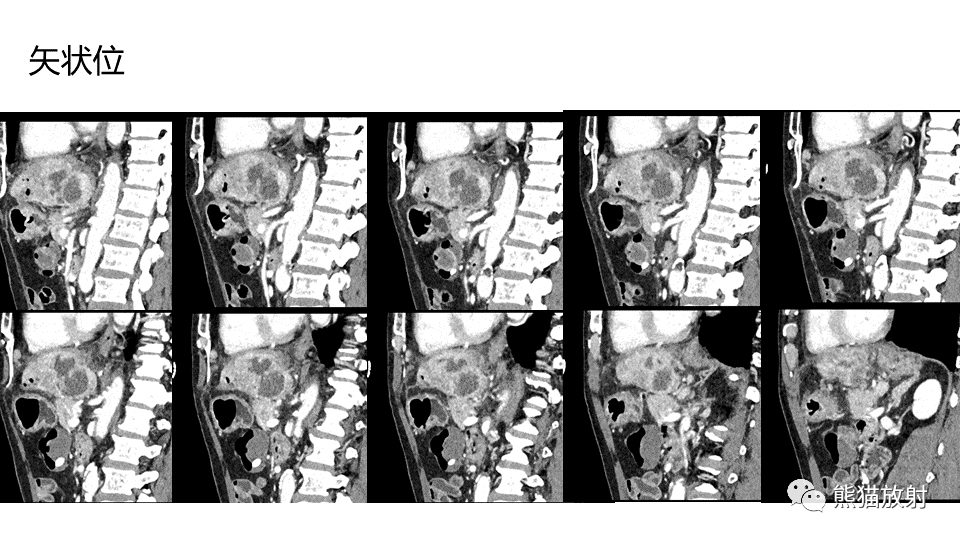

【PPT】肝内胆管细胞癌 VS 肝脓肿

【PPT】肝内胆管细胞癌 VS 肝脓肿-3